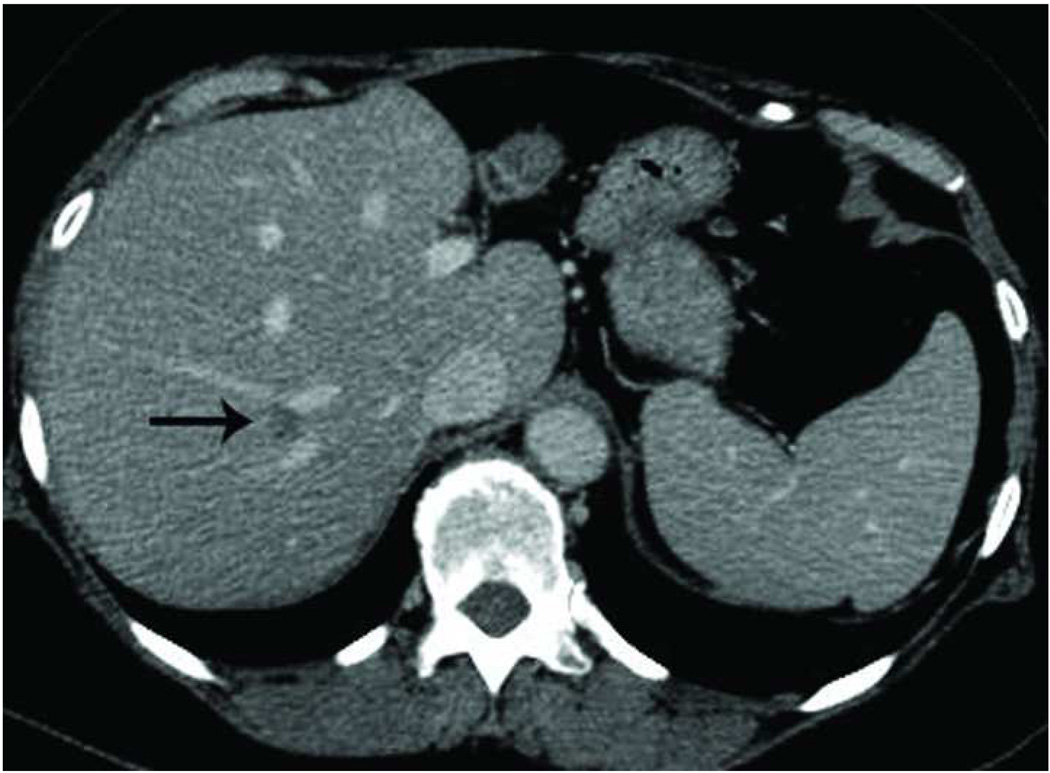

The liver is a vascular solid organ with an abundance of large vessels creating the potential for heat sink effects (Figure 5). Microwaves appear to be more apt to overcome perfusion and large heat sinks than other heat based ablation modalities (5, 10, 48–50). Microwave energy has been shown to ablate tissue up to and around large hepatic vessels measuring up to 10 mm and creates larger zones of ablation in high perfusion areas (5, 49–50). High perfusion rates in hepatic vessels greater than 3 mm limits the effectiveness of radiofrequency ablation, and has been shown to be an independent predictor of incomplete tumor destruction (51).

Figure 5.

Recurrence along a hepatic vein following RF ablation. Pretreatment CT image (a) demonstrates a small low attenuation lesion located between hepatic venous branches (arrow) concerning for metastatic disease in this patient with colorectal cancer. US image during treatment with RF ablation (b) demonstrates gas encompassing the small lesion. Follow up CT (c) demonstrates a low attenuation ablation zone (A) with local tumor progression along the margin abutting the hepatic vein (arrow).